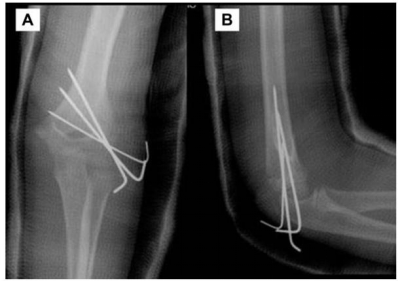

手术治疗-切开复位内固定

切开复位内固定:适用于>4mm移位,或2-4mm移位但闭合复位未达解剖复位者;采用肘外侧4-5cm切口,仅剥离骨折块前方肌肉止点(保护后方血供),清除血肿后复位,用克氏针经皮固定。

核心适应症:适用于Weiss III型骨折,或闭合复位失败者,特别是关节面软骨断裂或骨折块明显旋转情况。

常用手术入路:通常采用肘关节前外侧入路,或经典的后外侧Kocher入路,以获得最佳的骨折部位暴露视野。

精准复位与固定:直视下精确复位,使用克氏针或螺钉固定,确保关节面恢复平整,为功能恢复奠定基础。首选 3 枚光滑克氏针呈发散排列,稳定性优于平行排列。

图18示:克氏针固定示例(前后位与侧位)。可见多枚克氏针呈发散状穿过骨折块,提供稳定的力学支撑。